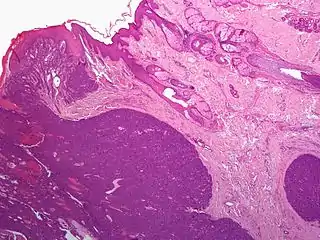

Gross pathology of a cystic nodular hidradenoma

Acrospiroma, solid type

Acrospiroma, clear cell type